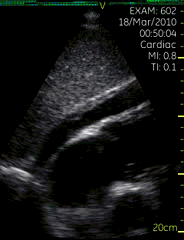

胸骨旁短轴切面

| 图像名称: | 胸骨旁短轴切面(二维) |

| 胸骨旁短轴切面 | | 介绍重点: | 短轴切面显示心肌向心性收缩运动 |

| 左室增大,室壁运动幅度降低; |

| 心包壁层脏层分离,右心室前方可见液性暗区 | | 临床用途: | 评估室壁厚度及运动;(正常图像) |

| 左室收缩功能降低 |

| 心包积液 |